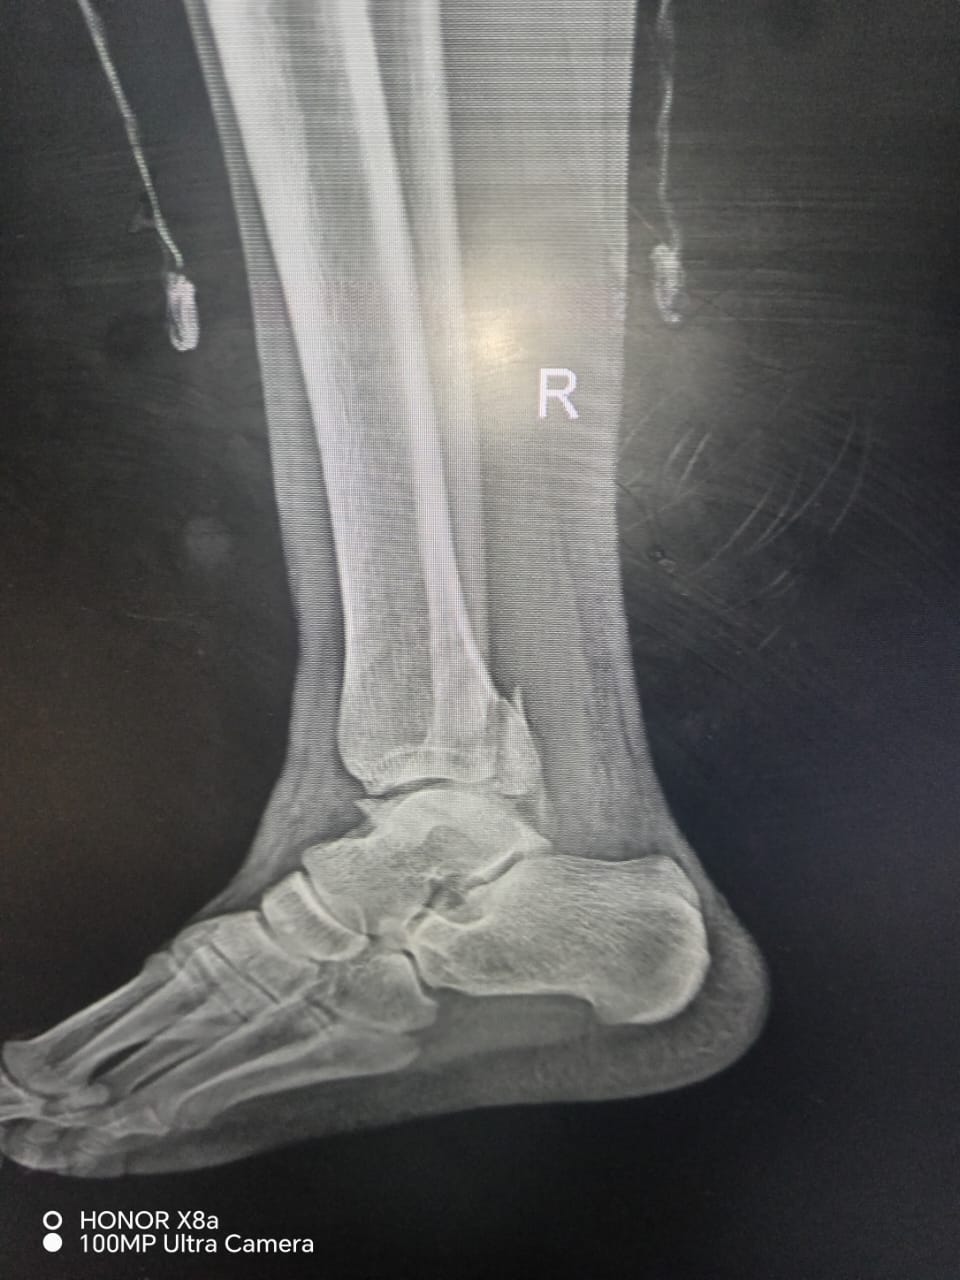

Rentgen müayinəsindən sonra vətəndaşa ayağında üç yerdən sınıq və ya qırıq olduğu bildirilərək mil (metall konstruksiya) taxılması məqsədilə əməliyyata cəlb olunub.

Məlumat üçün qeyd edək ki, vətəndaşın rentgen görüntüləri də redaksiyamıza təqdim olunub.